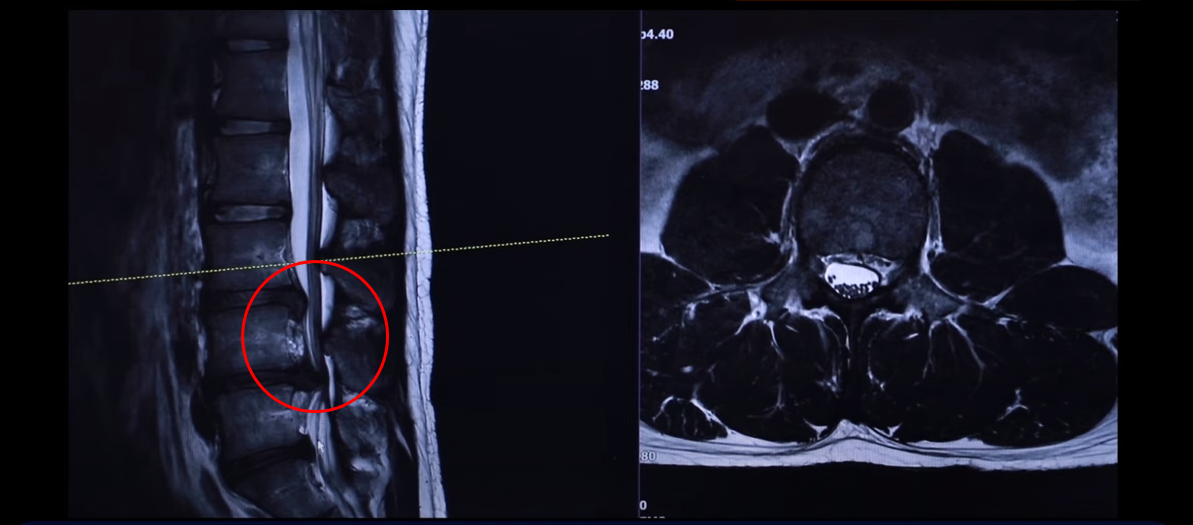

그 다음 마디 4번, 5번 보시면 보시다시피 아예 신경이 거의 보이지 않을 정도로 많이 밀려나왔습니다. 이렇게 심하게 파열된 경우를 보는 건 참 드뭅니다. 거의 신경이 보이지 않을 정도로, 오른쪽에 약간 하얀 부분이 남아 있습니다. 그래서 이 환자분 증상이 왼쪽 다리 증상입니다.

왼쪽 다리에 참을 수 없을 정도로 심한 방사통이 생긴 겁니다. 이분이 디스크가 왜 터졌냐? 24살이신데 어릴 때부터 허리가 아팠습니다. 고등학교 때부터 오랫동안 허리가 아팠기 때문에 나이에 맞지 않게 세 마디가 벌써 퇴행돼 있죠. 군대 때도 아팠고 최근에 중량 스쿼트, 웨이트 트레이닝 하다가 디스크가 터지게 됩니다. 웨이트 트레이닝 하다가 다리가 이상한 걸 느껴서 병원에 가서 MRI를 찍어 보니까 이렇게 심하게 터져 있습니다. 보통 이렇게 심하게 터져 있으면 어느 병원을 가든 정형외과나 신경외과에서 수술을 해야 된다 이런 얘기를 들을 가능성이 있습니다.